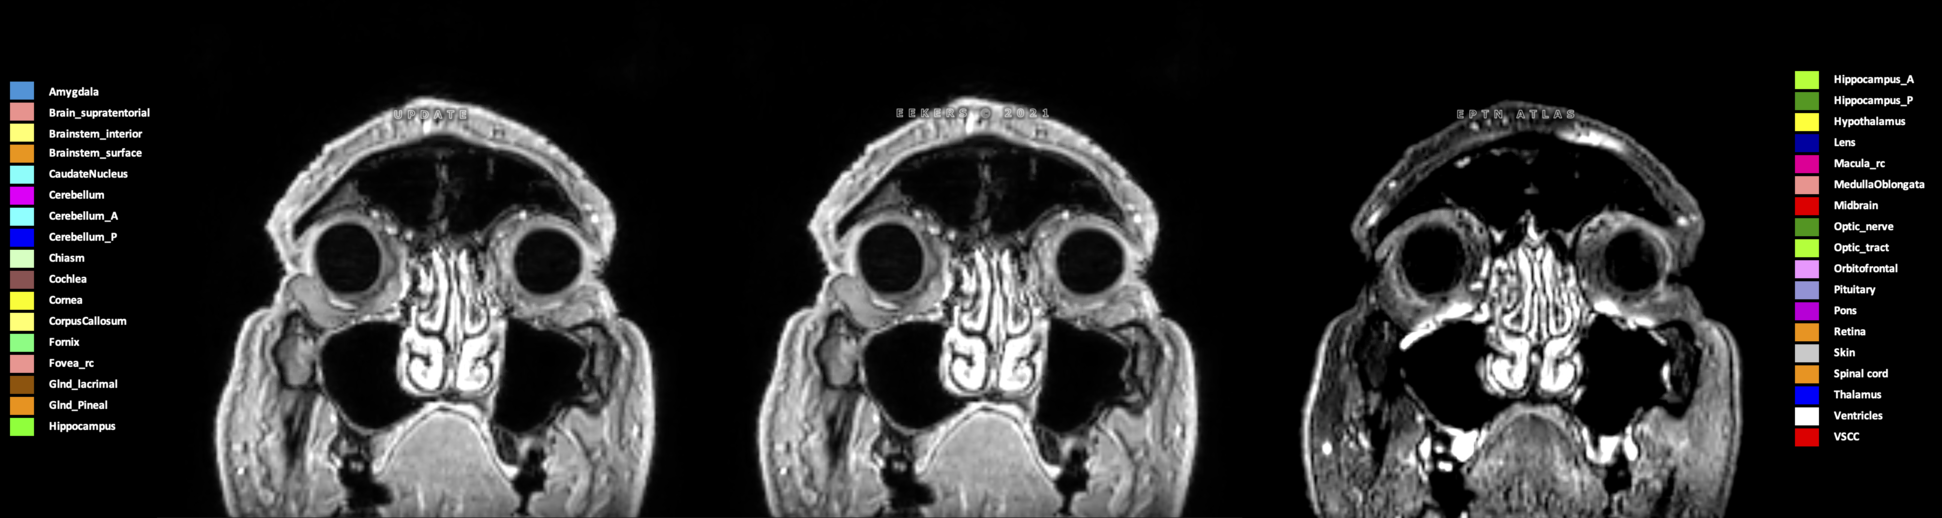

Eekers et al. have published an international neurological atlas for contouring of organs at risk in consensus with the European Particle Therapy Network (EPTN) in 2018 and an update in 2021. The purpose of this consensus atlas is to decrease inter- and intra-observer variability in delineating OARs relevant for neuro-oncology.

Included are all OARs known to be relevant for radiation-induced toxicity in neuro-oncology: brain, brainstem (midbrain, pons, medulla oblongata), chiasm, cerebellum (anterior & posterior), cochlea, cornea, hippocampus (anterior & posterior), hypothalamus, lens, lacrimal gland, optic nerve, pituitary, skin, and vestibular & semicircular canals. To further facilitate research on cognition, vision and radiological changes after irradiation of the brain, potential clinically-relevant OARs are included: amygdala, caudate nucleus, cerebellum (anterior & posterior), corpus callosum, fornix, macula, optic tract, orbitofrontal cortex, periventricular space (PVS), pineal gland, and thalamus.

Three-dimensional delineation of the 25 consensus OARs for neuro-oncology are shown on CT (WW/WL 120/40, 3000/600), 3T MR images, (T1Gd, T2FLAIR 1mm) and 7T MR (MP2RAGE 0.7 mm). All are presented in transversal, sagittal and coronal view.